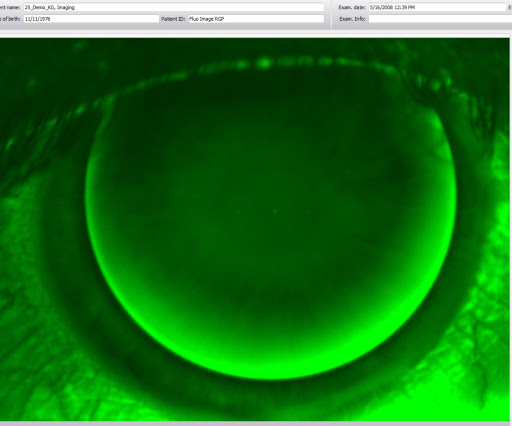

I am so glad that I found Dr. Tran. I had lasik-induced keratoconus and the only remedy I knew of was RGP lenses, which caused me continual torment, because of my severe dry eyes. I had only recently heard of Sclera lenses as a solution for those with dry eyes and/or keratoconus, when I set out on a mission to find a doctor in the DFW area I felt comfortable with. I narrowed my search to a handful - some were recommended and some I found via an internet search. I interviewed each of the doctors in my search list. All were impressive, but there was something special about Dr. Trans answers. His concern for my suffering was readily apparent in his answers and in his questions back to me. I knew he was the doctor for me. He made every accommodation to my quirky scheduling problems, which I found quite refreshing. He could not have been more pleasant nor have been more thorough in his exam. Sclera lenses require several fittings and he patiently listened to my every concern. The result: my fitting and eyesight are perfect. I can wear the sclera lenses all day long without discomfort. The bottomline is this: If you need correction, you can be assured that you will get a thorough and very competent exam and fitting with Dr. Tran. I heartily recommend him.

Awesome customer service and state of the art equipment They have machines that most optometrist wished they had. No more blowing in the eye pressure machines. Only high tech equipment with back of eye image scanning technology. I was impressed so I will be sure to recommend them to all my friends and family.